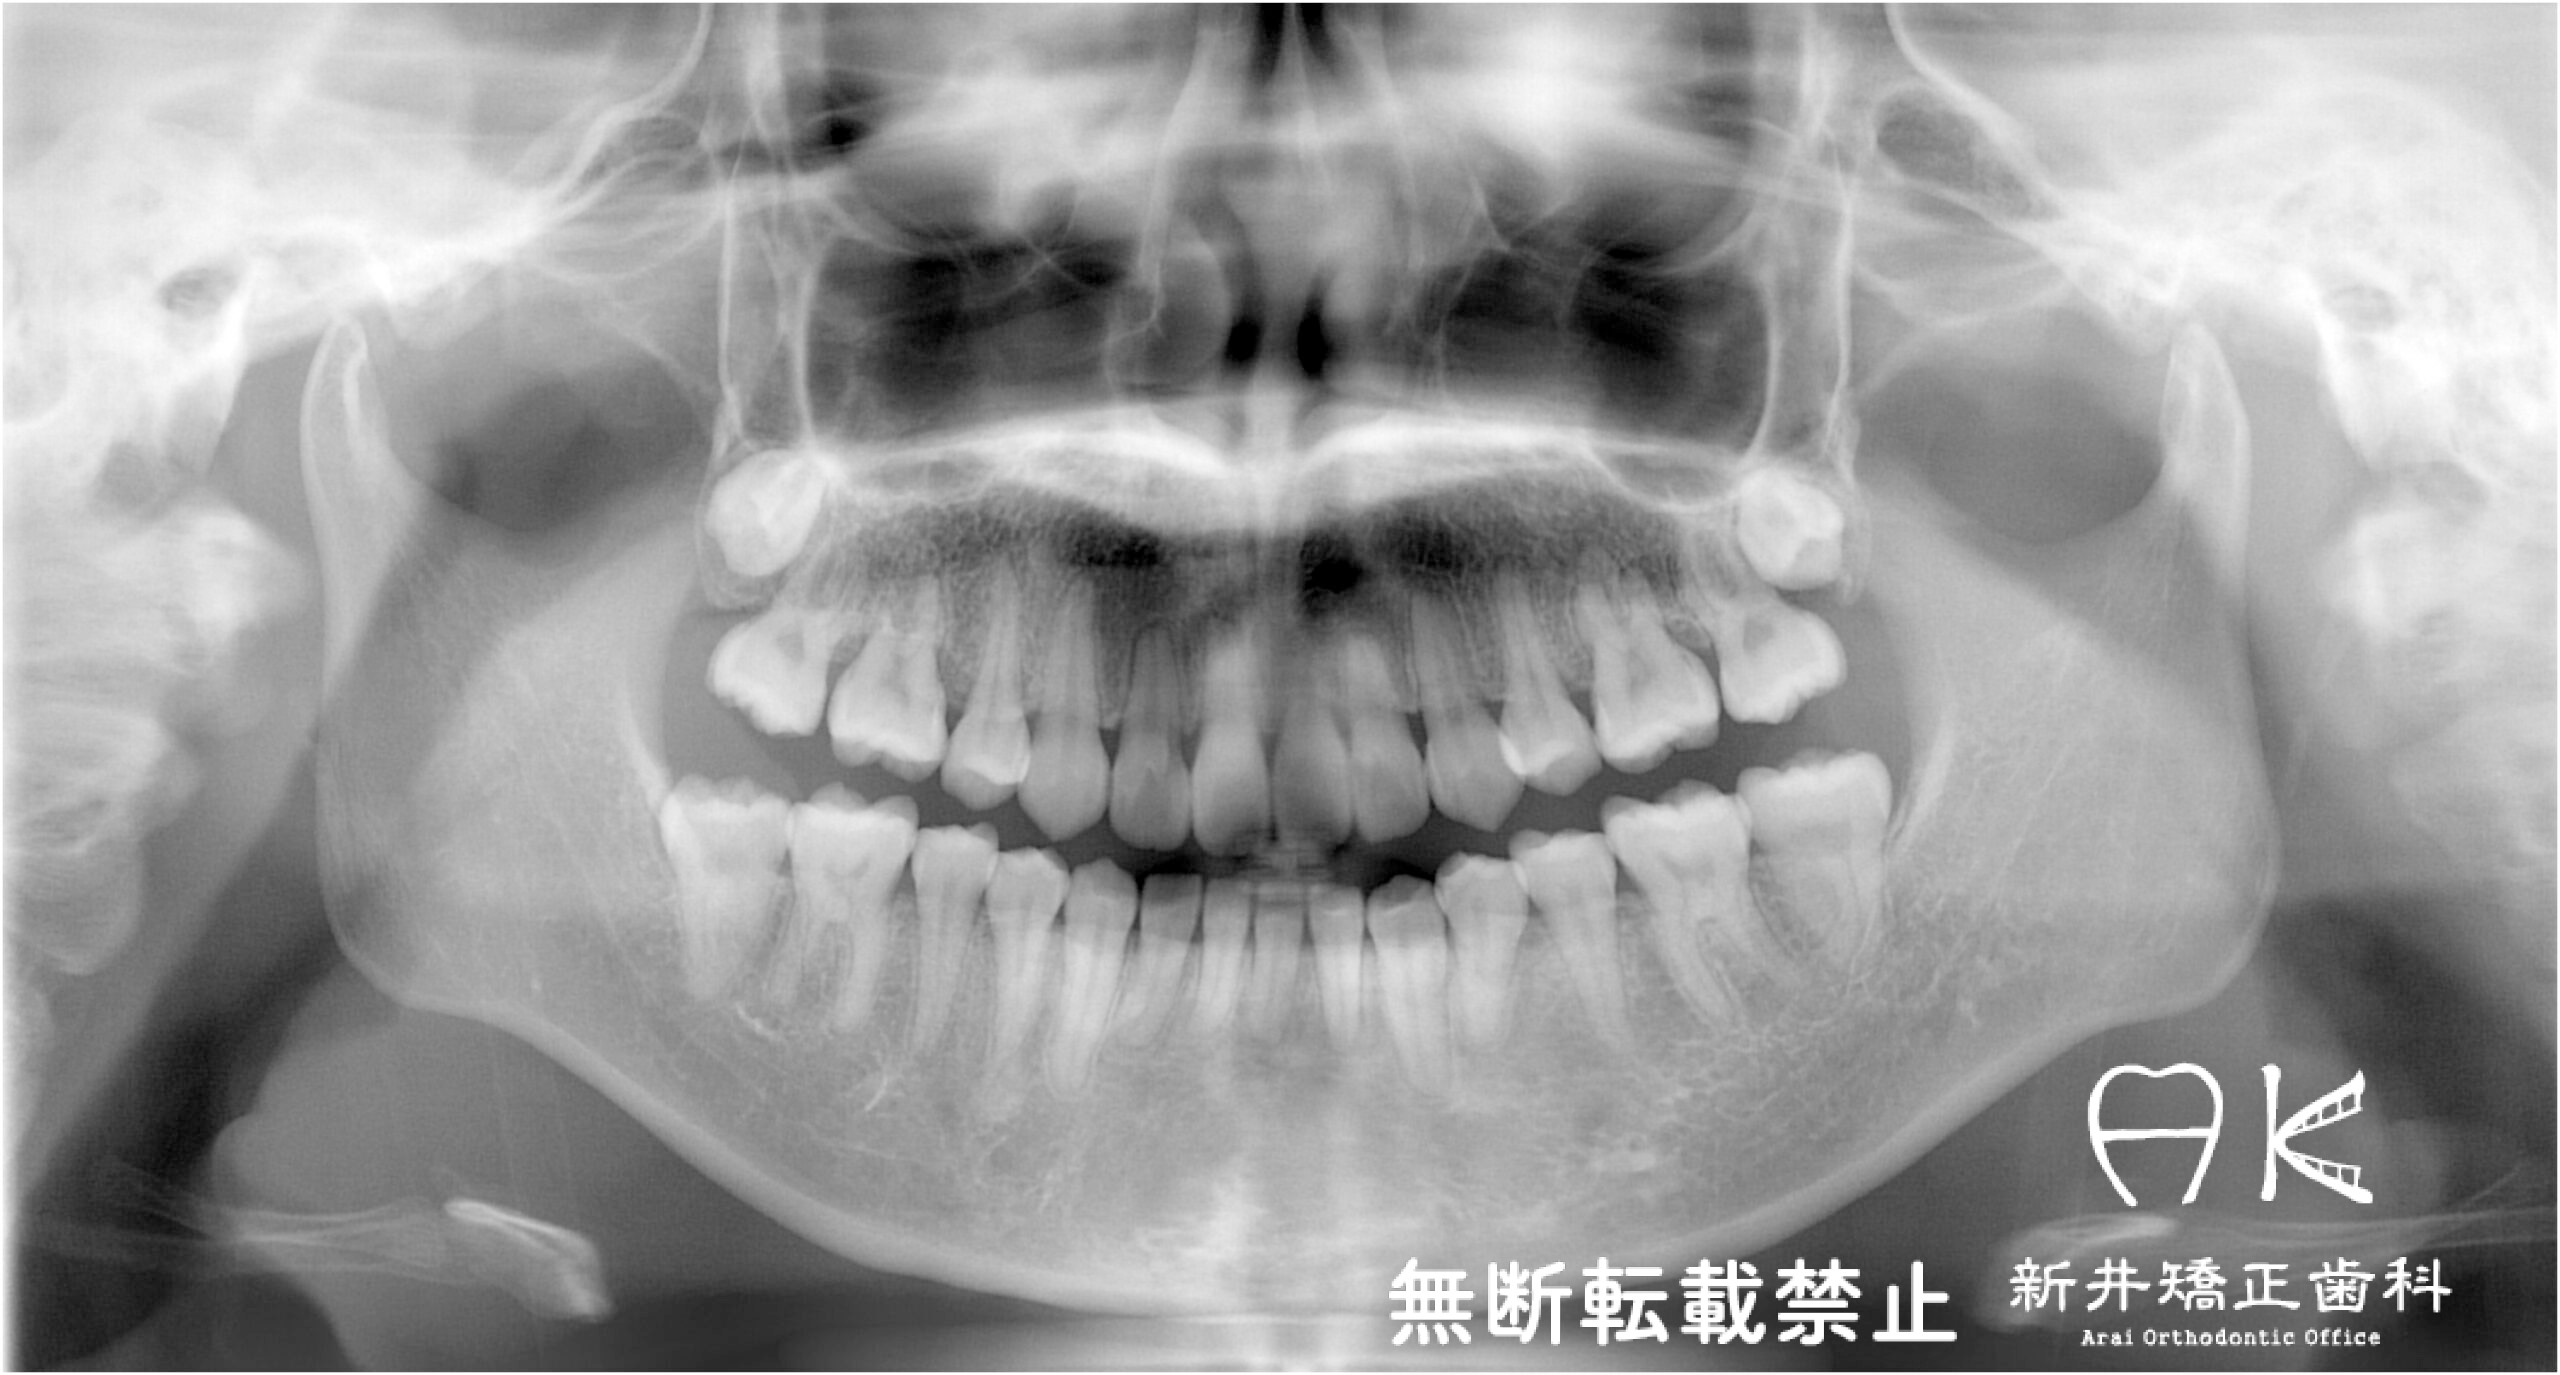

治療内容

| 症状・診断名 | 叢生 |

| 抜歯の有無 | 上下左右第一小臼歯(前から4番目の歯) 上下左右第三大臼歯(親知らず) |

治療前後の解説

| 治療前 | でこぼこしている歯による歯磨きのやりにくさや、奥歯がしっかり咬んでいない鋏状咬合(すれ違い咬合)。 出っ歯による口の閉じにくさ(口唇閉鎖不全)と、正面から見た時のオトガイ部にできる梅干し様のシワやイーラインから飛び出た口元(口ゴボ)。 機能面も審美面も気にしていた患者さんです。 治療中もなるべく装置を目立たせたくないため、ハーフリンガルでの治療となりました。 |

| 治療後 | 上下の歯がお互いにはまり込み、全体的に緊密な咬み合わせになっています。 出っ歯が治り、口元の突出感が改善されて綺麗なEラインを獲得しました。 すれ違い咬合や叢生(歯のでこぼこ)も治って歯磨きがしやすく、嚙みやすい状態になっています。 |